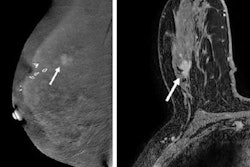

Another article drawing attention in our Women's Imaging Community featured new research comparing an abbreviated breast MRI protocol with standard breast MRI and contrast-enhanced mammography (CEM) in supplemental breast cancer screening. Although abbreviated MRI performed comparably to standard breast MRI, CEM showed some benefits as well as drawbacks.